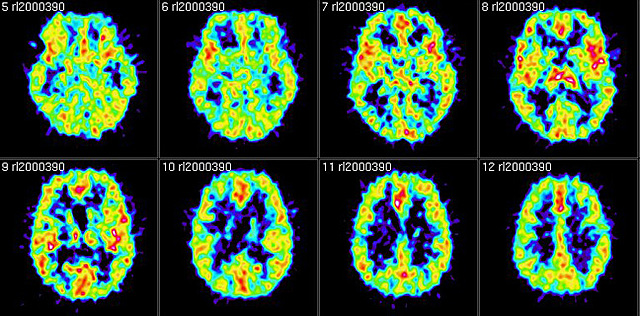

Se fortalece la investigación con el empleo de imágenes no ya anatómicas sino funcionales, en particular la resonancia magnética funcional (fMRI, por sus siglas en inglés) y la tomografía por emisión de positrones (PET), que han permitido visualizar la actividad cerebral durante la realización de diferentes tareas cognoscitivas(por ejemplo, hablar, leer, pensar en palabras, etc. Ardila y Rosselli, (2007)